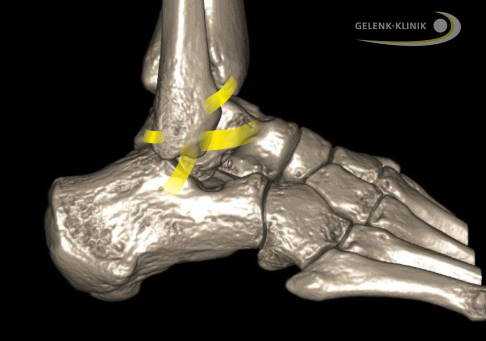

Внешние связки соединяют малоберцовую кость (Fibula) с пяточной и таранной костями. Межберцовый синдесмоз проходит между большеберцовой и малоберцовой костями. © Gelenk-Klinik

Реконструкция связок голеностопного сустава является операцией по лечению хронической нестабильности. Эта нестабильность приводит при малейших нагрузках к вывихам лодыжки. При этом наблюдается повышенная подвижность самого голеностопа, что является большей нагрузкой на суставный хрящ, что обычно, и приводит к его разрушению.